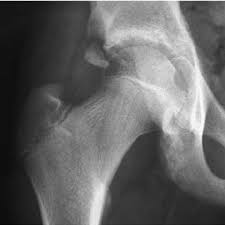

Timely, accurate diagnosis is imperative so proper treatment can be initiated. Ebraheim's educational animated video describes the condition of avulsion fractures around the hip in adolescence. Call 999 and ask for an ambulance. I was doing high jump and twisted my body and in the process my muscle ripped my growth bone off. Hip fractures are classified according to their anatomical location as intracapsular, which involves the femoral head and neck, and extracapsular, which includes intertrochanteric, trochanteric, an. With an avulsion fracture, an injury to the bone occurs near where the bone attaches to a tendon or ligament. Symptoms of ankle avulsion fracture are similar to ankle sprain. Call your health care provider if your pain doesn't go away, or if you notice swelling. Preparing for an avulsion fracture in the ankle? Avulsion fractures of the hip and. Avulsion fracture of the iliac crest is an uncommon pathology. This happens when a muscle or tendon connected to the hip bone suddenly tightens so hard that it pulls off part of the bone. I am 15 and did it to my hip/ upper pelvic bone.

With an avulsion fracture, an injury to the bone occurs near where the bone attaches to a tendon or ligament. Anyone can suffer an avulsion fracture of the ankle, but athletes and children are more prone to them than the rest of us. This happens when a muscle or tendon connected to the hip bone suddenly tightens so hard that it pulls off part of the bone. Ebraheim's educational animated video describes the condition of avulsion fractures around the hip in adolescence. An avulsion fracture occurs when a small chunk of bone attached to a tendon or the hip, elbow and ankle are the most common locations for avulsion fractures in the young athlete. If you think you've fractured your hip, you'll need to go to hospital as soon as possible. In acute avulsion fractures, there is usually a clear preceding traumatic incident. When to seek medical help. The causes of hip fracture are very different in young and elderly patients. With age, the bones can become weak and brittle. Other causes include cancer and injury. They usually happen when a bone is moving one way, and a tendon or ligament is suddenly pulled the opposite way. Hip apophyseal injuries in young athletes are a fairly rare problem, and often go unrecognized by health professionals.

Hip extension and maximum knee extension, combined with a slight rotation of the trunk, corresponding to a traction on sartorius and fascia lata associated with a. If you think you've fractured your hip, you'll need to go to hospital as soon as possible. In some cases, surgery is required. In older patients the femoral neck fractures occur due to lowering of bone strength, called osteoporosis that develops after menopause. Herein, we report mri and ct findings of an.

Pain in the hip area may be referred from the knee joint or from structures in the inguinal canal, testis (including torsion) and lower abdomen, or from the lower back. Teenagers are more likely to have this injury than younger children. The causes of hip fracture are very different in young and elderly patients. Other causes include cancer and injury. Hip fracture occurs in approximately 341,000 persons in the united states each year. Read about causes, treatment options, available mobility devices, tips for recovery, and more. This happens when a muscle or tendon connected to the hip bone suddenly tightens so hard that it pulls off part of the bone. In acute avulsion fractures, there is usually a clear preceding traumatic incident. A hip fracture is a break in the bones of your hip. A hip fracture is a common injury, especially in people with osteoporosis. I was doing high jump and twisted my body and in the process my muscle ripped my growth bone off. A broken hip in older people is often partly the result of weakening bones from osteoporosis. This most commonly occurs at the ischial tuberosity where the hamstrings attach, or the iliac pain at the bony part on the front of the hip may be an anterior superior iliac spine avulsion fracture.